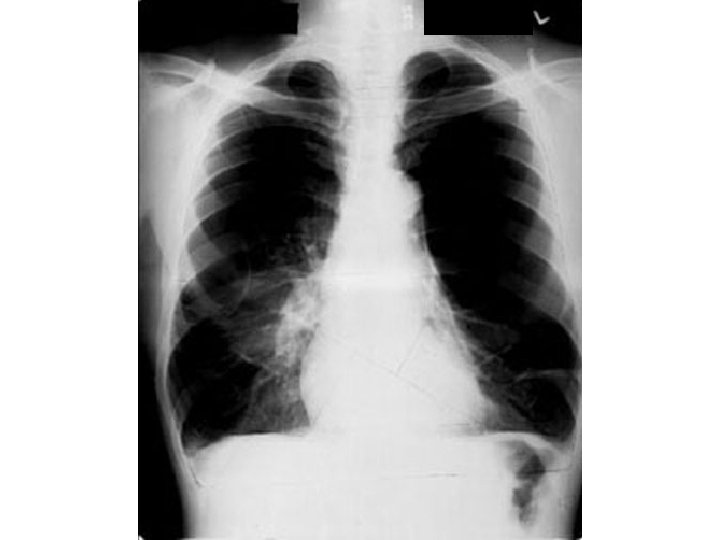

Case 1